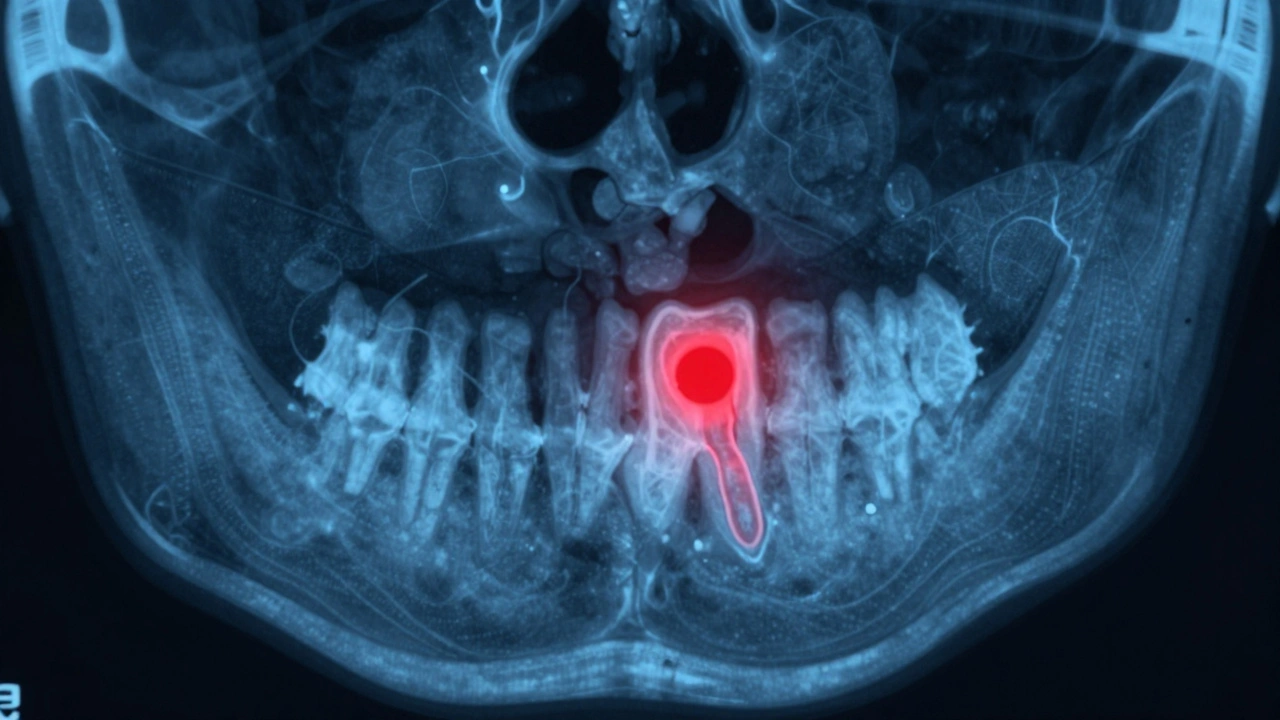

3D CT snímek čelisti s červenou skvrnou ukazující skrytou infekci kolem kořene.

Co dělat, když zub po ošetření bolí, ale zubař nevidí nic na rentgenu?

Toto je častý případ. Někdy rentgen neukáže nic - ale vy to stále cítíte. Proč?

Protože některé problémy nejsou vidět na běžném rentgenu. Například:

• Malá trhlina v kořeni

• Chyba v plnění, která je jen 0,1 mm široká

• Zánět v tkáni, který ještě nezpůsobil změny v kosti

V takovém případě je potřeba přesnější vyšetření - například 3D CT rentgen. Ten ukazuje zub v třech rozměrech a umožňuje najít problémy, které běžný rentgen přehlíží. Pokud máte možnost, neváhejte požádat o tento typ snímku. Je to důležitý krok, pokud bolest přetrvává.